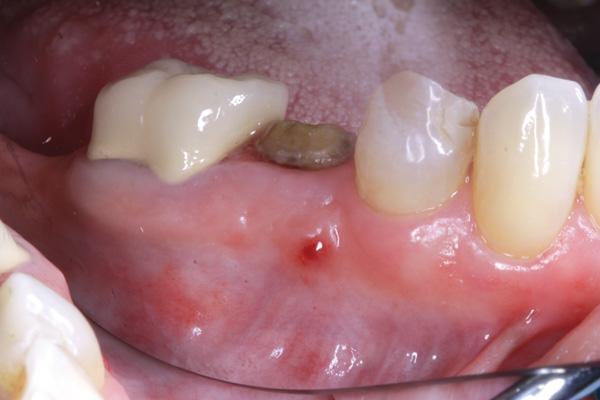

Manifestations of acute infection include abscess and cellulitis. Abscess is an accumulation of pus in an enclosed space7 (Figure 1), while cellulitis is a diffuse inflammatory process within tissues, which may manifest edema, redness, pain, and interference with function (Figure 2). With cellulitis, the infection may be caused by various organisms, and it typically occurs in loose tissues beneath the skin or mucous membranes or around muscle bundles or surrounding organs.7 Also with cellulitis, the severity of the infection is initially determined by virulence of invading bacteria and the host’s response.

A periodontal abscess usually manifests itself as red, painful swelling adjacent to a tooth, where it is typically associated with deep probing depths; a draining fistula is rarely present. In contrast, an endodontic abscess often demonstrates an inflamed fistulous tract, which is typically apical to the mucogingival junction. In a radiograph, there often is radiolucency at the apex of the tooth.

Figure 1 Fistulous tract at tooth No. 30 associated with an endodontic-periodontal abscess. When palpated, the fistulous tract may express pus. Usually, a periodontal abscess will not have a fistulous tract. Its appearance usually reflects an endodontic etiology causing the lesion. (Photograph courtesy of Dr. Mehmet Dikman.)

Figure 1